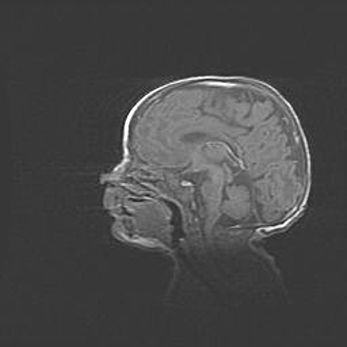

Наружная гидроцефалия с возможной атрофией височных областей.

Возраст: 28 дней

Вес: 3670 г

Пол: мужской

Окружность головы: 38 см

Срок гестации: 40 недель

Гидроцефалия головного мозга у новорожденных – это заболевание, которое характеризуется скоплением избыточного количества спинномозговой жидкости в желудочковой системе головного мозга в результате затруднения её перемещения от места выработки к месту поглощения в кровеносную систему или вследствие нарушения абсорбции. При открытой наружной форме гидроцефалии у новорожденных расширяются и переполняются субарахноидные пространства.

При нормотензивных  формах,  которые,  как  правило,  являются  следствием  перенесенных ишемических  повреждений  паренхимы  мозга,  возможно  сочетание микроцефалии  с нормотензивной гидроцефалией. В основе данных изменений лежит атрофия больших полушарий с преимущественной  локализацией  в  лобно-височных  областях.